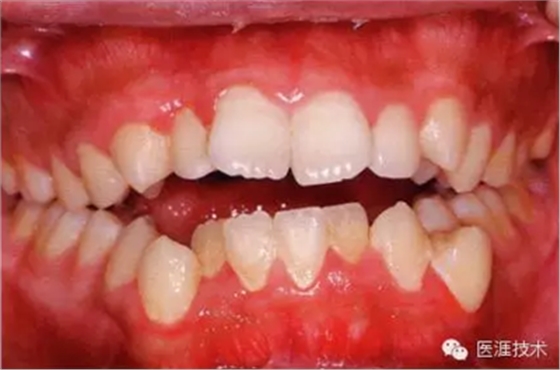

健康且正常的牙周組織臨床圖像

50歲女性的健康口腔內(nèi)部

圖為50歲女性,無(wú)特殊全身疾病,不抽煙。持續(xù)保養(yǎng)6年。無(wú)填充物等問(wèn)題,依照患者本人要求持續(xù)觀察。牙周組織臉頰側(cè)雖見(jiàn)部分萎縮,但X線牙片顯示牙間無(wú)骨吸收現(xiàn)象,保持著比較健康的狀態(tài)。